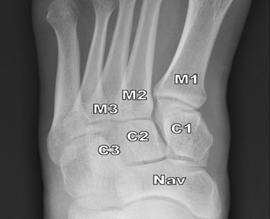

1.Lisfrac关节正常X线(负重位):M1与C1外侧缘对齐;M2与C2内侧缘对齐;C1-M2、M1-M2间距小于2mm。